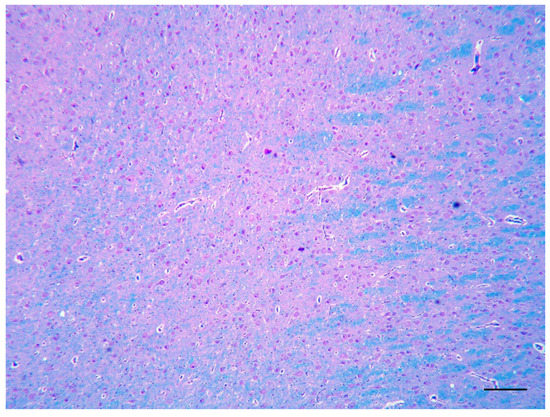

Three cases of the malformation of the cortical development are described: a mixed breed dog and a Border Collie pup with a focal and diffuse cortical dysplasia, respectively, and a kitten with lissencephaly. All cases presented with intractable epilepsy and were euthanized, due [...] Read more.

Three cases of the malformation of the cortical development are described: a mixed breed dog and a Border Collie pup with a focal and diffuse cortical dysplasia, respectively, and a kitten with lissencephaly. All cases presented with intractable epilepsy and were euthanized, due to the cluster of epileptic seizures. The gross examination at necropsy revealed the morphologic alteration of the telencephalic region in two cases. Histopathologically, a disorganization of the cortical lamination with the presence of megalic neurons, was found in the focal cortical dysplasia case. An altered organization of the white and gray matter, with a loss of the normal neuronal distribution and altered neurons, characterized the diffuse cortical dysplasia case. In the lissencephalic cat, there was no recognizable organization of the brain with areas of neuroglial tissue forming nodules in the leptomeningeal space. We strongly support the hypothesis that, as in humans, as well as in the veterinary patients, malformations of the cortical development could be the cause of refractory epilepsy. Full article